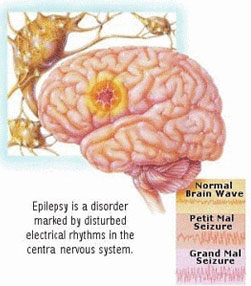

Many medical issues, including tumours, clots, aneurysms, seizures, and Parkinson's disease, can be treated with brain surgery or neurosurgery...